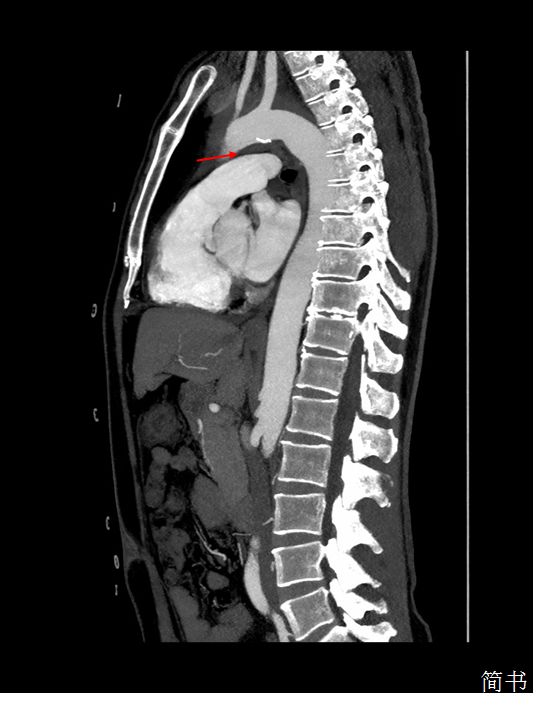

回过头来看我们这位患者,从主动脉CTA矢状位上能够发现主动脉弓与肺动脉间隙被壁内血肿填充(图*箭3**头处),解剖学上左侧喉返神经正好走形在此处,受到主动脉弓血肿压迫导致声带麻痹。至此,拨开疑云见日照,患者的突发声嘶是由于——继发于主动脉壁内血肿的心脏-声带综合征。

图3 主动脉CTA矢状位:箭头所指部位为主动脉弓与肺动脉间隙,可见该间隙被壁内血肿填充,左侧喉返神经从该间隙环绕主动脉弓后折返向上走形